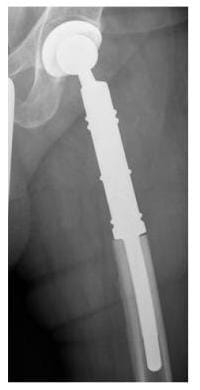

Röntgenbild Ersatz des Hüftgelenkes und oberen Anteils des Oberschenkelknochens durch eine Prothese

Ersatz des Hüftgelenkes und oberen Anteils des Oberschenkelknochens durch eine Prothese.

(Bild: Orthopädie)